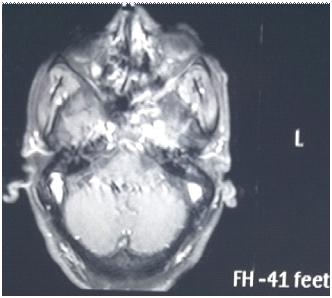

Among the metabolically abnormal patient’s population 20% (n=3) had Hypoglycemia, 40%(n=6) presented with Dyselectrolytemia, 26.67% (n=4) had Uremia, 13.33% (n=2) presented with Hepatic encephalopathy. Overall, 31 patients underwent Lumber puncture, of which CSF report shows abnormality in 11 (35.48%) cases and normal in 20 patients (64.51%). Abnormal CSF report suggesting viral meningoencephalitis found in 46% (n=5), bacterial meningitis in18% (n=2), Tuberculous Meningitis in 27% (n=3), Aseptic meningitis in 9% (n= 1). All 65 subjects underwent CT scan brain among which MRI Brain also done in 55 cases. CT findings is normal in 44.62% (n=29), abnormal in 55.38% (n=36). The most common CNS lesion on CT scan was infarction in 10.77% followed by ring lesion in 9.23% and intracerebral Hemorrhage in 7.96%. We observed cerebral infarction is causative factor of Seizure in female (15%) but intracerebral hemorrhage and ring lesion are most common findings in male, comprising 11.11% patients at each category. The CT scan in new onset Seizure of elderly patient population revealed Infarction in 28.57%, Gliosis in 19.04% and cerebral atrophy in 14.28%. The breakup of findings in MRI Scan of 55 patients shows Hyperintensities on T2, indicating Demyelination / Inflammation/edema in12.31% followed by infarction in 10.77% and ring lesion in 9.23%. In the female population, hyperintensities on T2 MRI found in 15% and Infarction in 15% whereas among the males intracerebral Hemorrhage, Ring lesion and hyperintensities on T2 found at similar occurrence rate @11% in each of these three types of lesions. EEG was done on 80% patients (n=52) of whom 22 patients has abnormal discharge in EEG but 30 patients have normal presentation. Among 65 patients one female expired due to Acute Demyelinated Encephalomyelitis (ADEM) and two males expired one due to Hemorrhage, another one with CNS infection when undergoing treatment indoor.

We found a strong positive correlation between abnormal EEG and abnormal Neuroimaging with Correlation coefficient of 0.902, (P- Value 0.0138) but almost no correlation found between normal EEG with normal Neuroimaging (Figs 1-4).

About 23% of patients with adult onset first seizure has metabolic derangement and the most common etiology was Dyselectrolytemia. The most common Central Nervous System (CNS) Infection as detected by CSF study was viral meningoencephalitis followed by Tuberculous Meningitis. The most common CNS lesion detected by CT studies as well as by MRI Brain was infarction and ring lesion, the two Neuroimaging studies corroborated in 75.38% of Seizure patients. Abnormal discharge in EEG found in34% cases. In majority patients EEG report was normal. EEG abnormality was more common in patients with Focal Seizure rather than GTCS patients. Thus, the most common etiology of first Seizure onset at adult age over 18 years were metabolic derangements (16.92%), CNS Infection or Inflammation (15.38%) and intracerebral Space occupying lesion (15.38%), usually ring lesion, tumors and Metastasis. Idiopathic Seizure found in 7.69% patients. The Correlation between abnormal Neuroimaging and abnormal EEG is strongly positive and statistically significant (P -Value = 0.013) but the same is not true in cases of normal Neuroimaging and normal EEG findings.